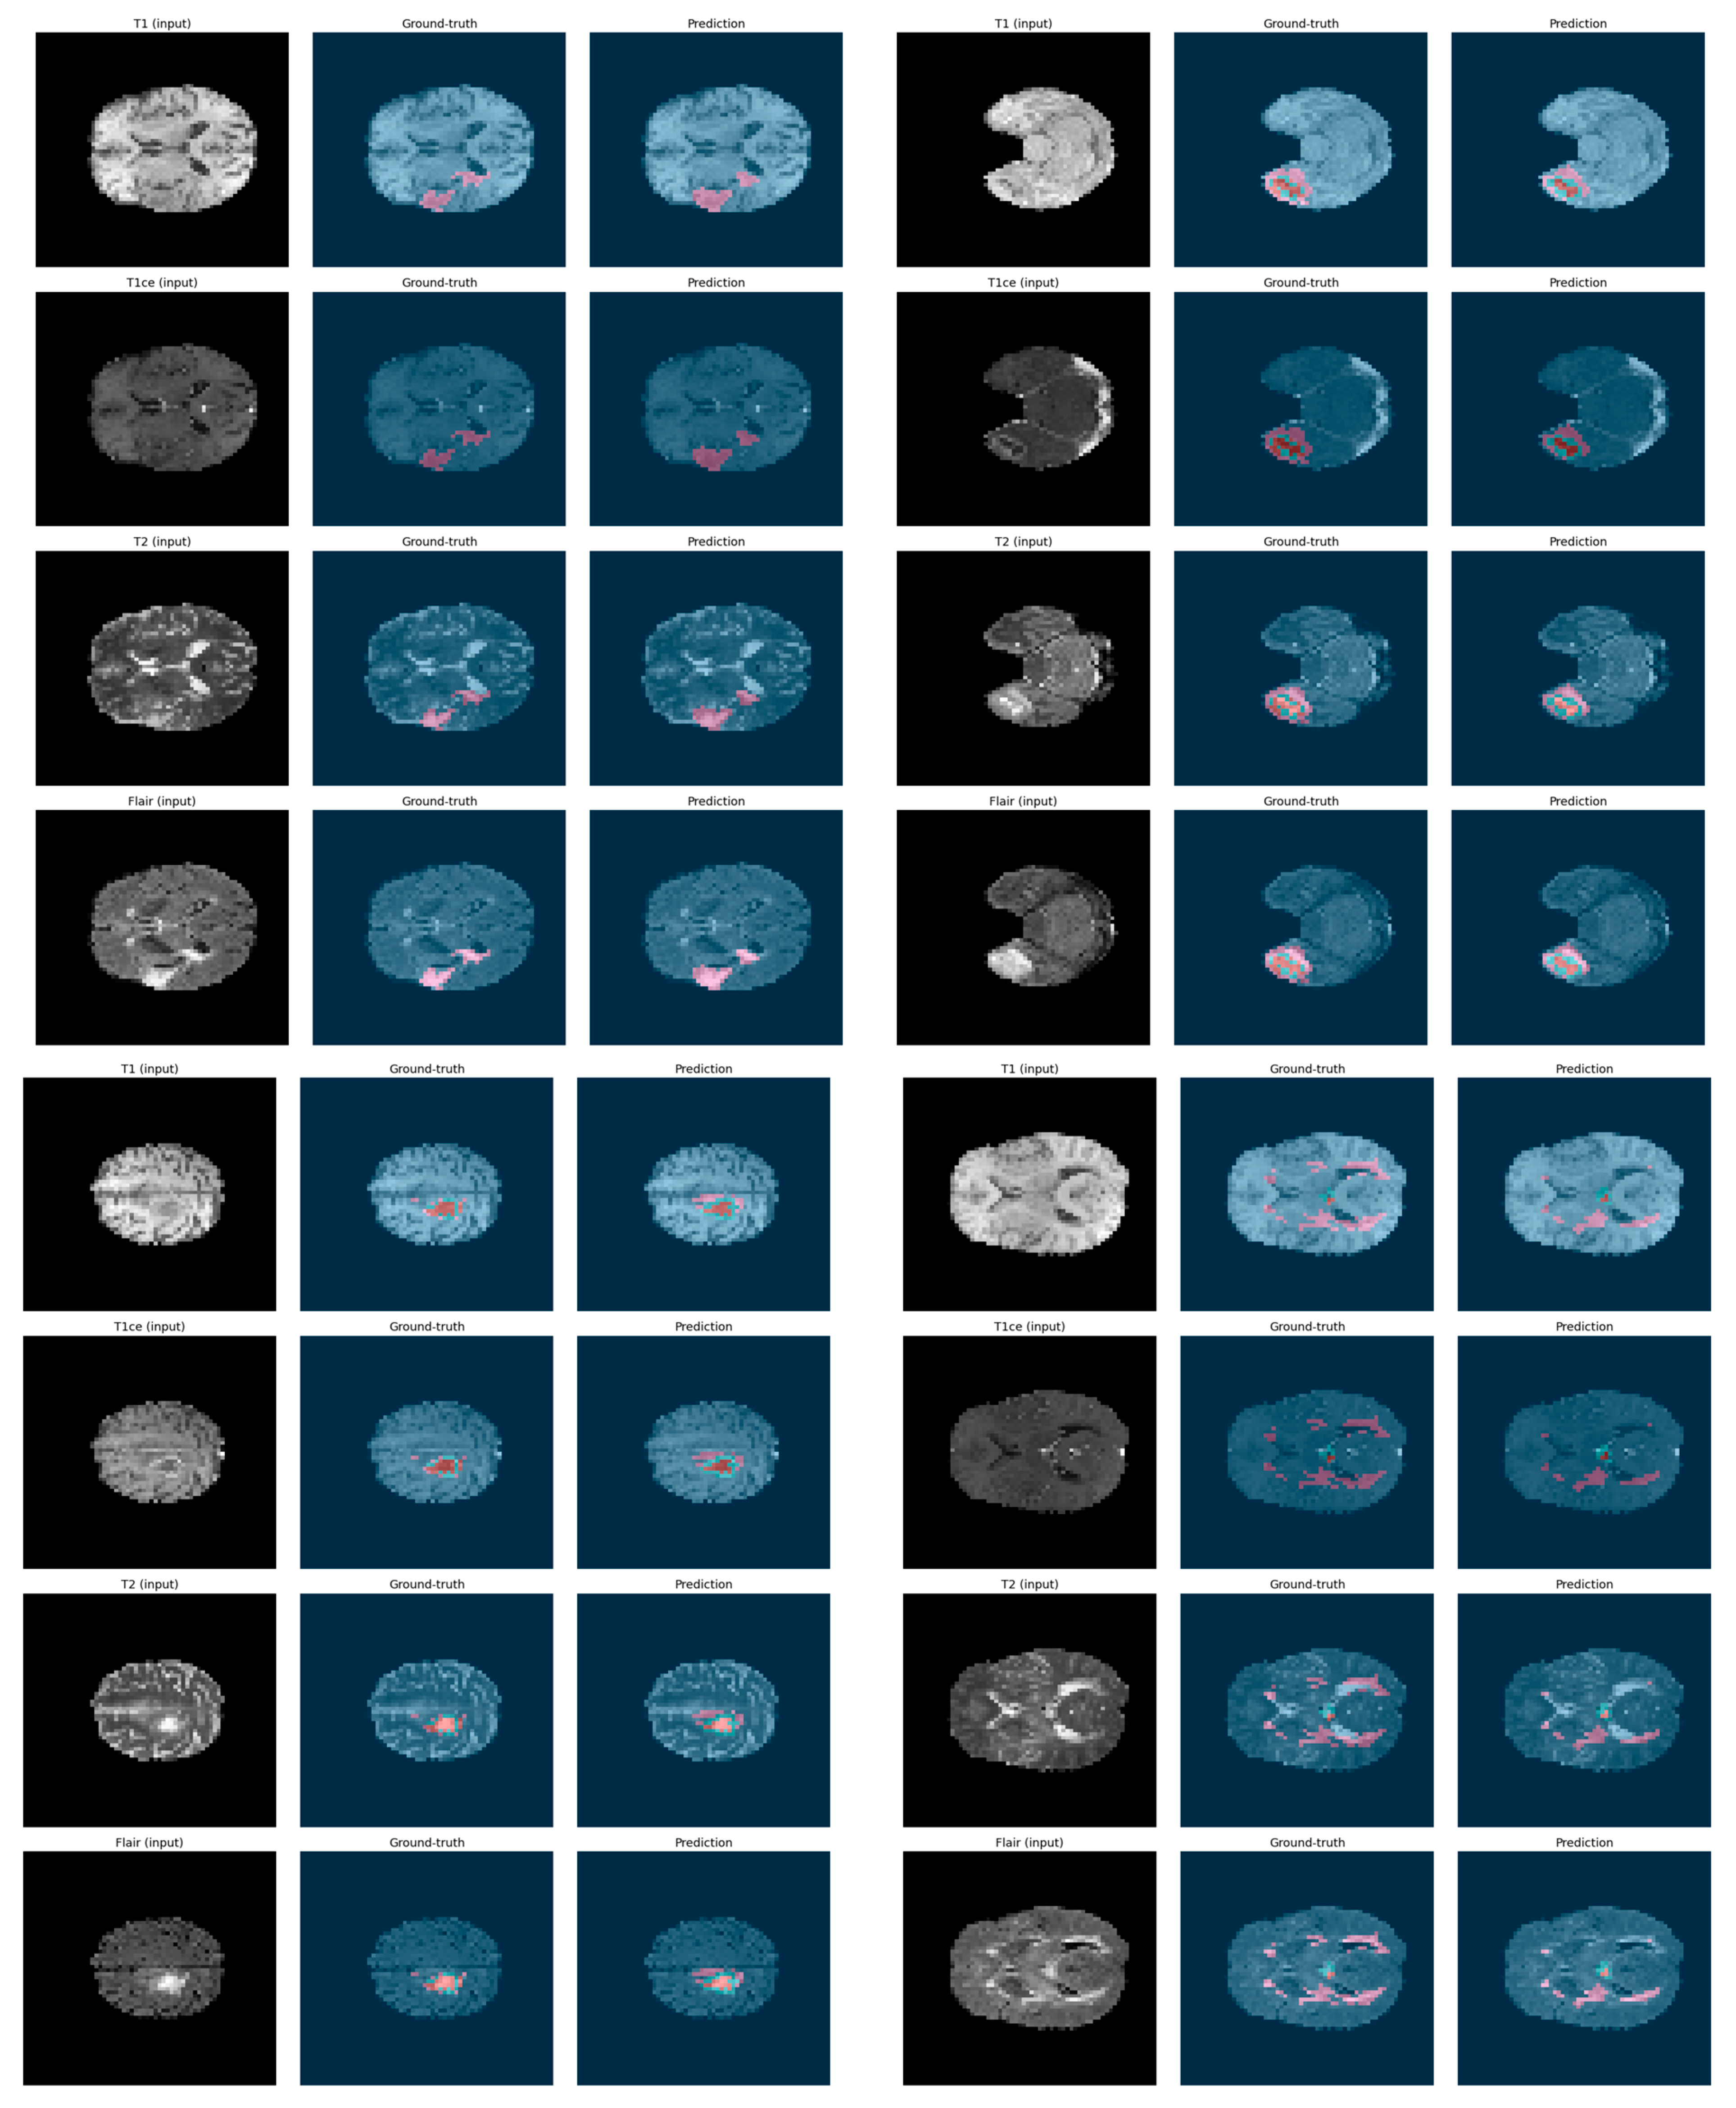

5.3. Qualitative Visualization